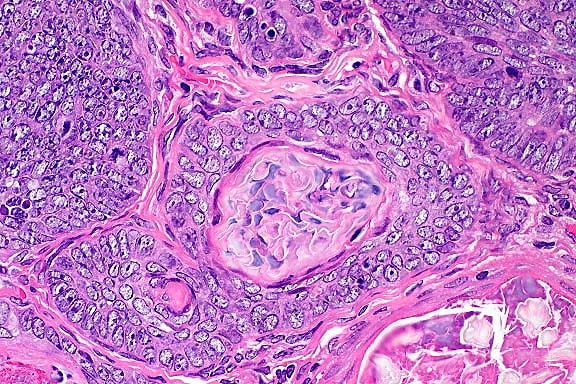

10x

obj

- Case 13-1. Skin. Numerous hair follicle-like structures

expand the dermis.

40x

- Case 13-1. Dermis. There are glassy basophilic intranuclear

inclusions within more mature central cells of follicle.

- AFIP Diagnosis: Haired skin: Benign hair follicle

tumor, with few intranuclear inclusion bodies, golden Syrian

hamster (Mesocricetus auratus), rodent.

- Conference Note: An unencapsulated, well-circumscribed,

multilobulated neoplasm expands the dermis and subcutis, and

compresses subjacent skeletal muscle. The neoplasm is composed

of lobules of epithelial cells arranged in nests, broad cords

and hair follicle-like structures. A peripheral layer of basophilic

polygonal cells aligns along the basement membrane, and neoplastic

cells are more eosinophilic within inner layers of the abortive

hair follicles. Small numbers of intranuclear inclusions are

within the more mature, inner layers of neoplastic follicular

epithelium.